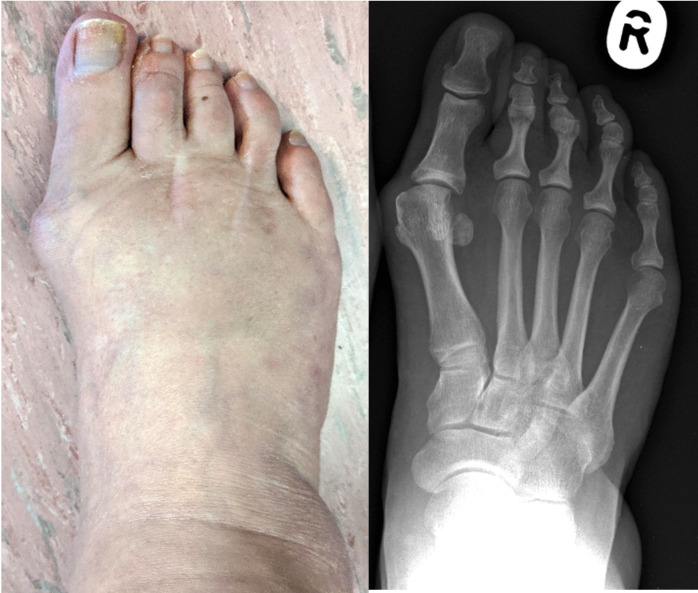

Aims: Hallux valgus (also known as a bunion) is a common forefoot deformity impacting pain, function, quality of life, and mobility, with higher prevalence in females and increasing incidence with age. The high prevalence and rates of surgical treatment potentially have a major impact on the healthcare system. The aim of this stakeholder consultation was to identify current issues with provision of hallux valgus treatment, as well as identify achievable goals to improve understanding of hallux valgus and guide future assessment, treatment pathways, and research directions with the aim of improving clinical outcomes for patients.